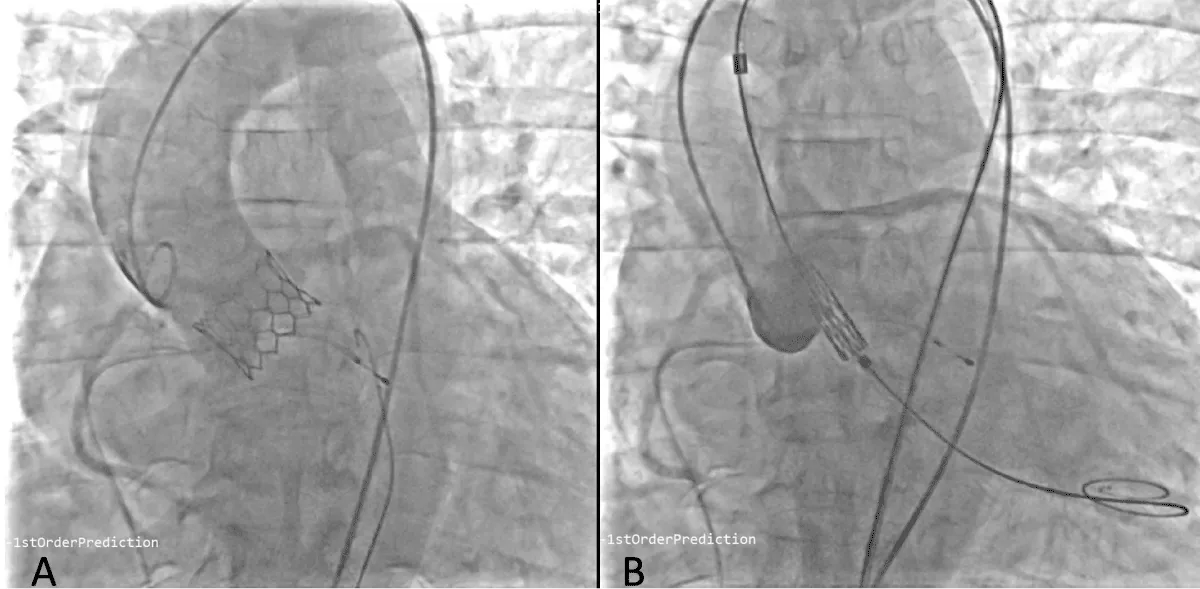

After obtaining consent, access was obtained through the right femoral vein and artery. Under 4D Transesophageal Echocardiography (4D TEE) guidance, the first transseptal puncture was performed with a broken Brough needle, and the LA wire was inserted through femoral venous access (Figure 1). Right femoral artery access was used for retrograde crossing of the aortic valve (AV) (Figure 2), and a Teflon wire was placed in the left ventricle. The aortic valve (AV) was dilated with a 14 mm ATLAS GOLD (BARD) balloon (Figure 3, Video 1).

Download Image

Figure 1: A,B: 4Dimensional multiplanar transoesophageal echocardiography. A. 4D image with Left atrial wire, B. Severe mitral stenosis with mitral area of 0.5 cm2, 1C &1D. Showing multiplane of mitral valve.